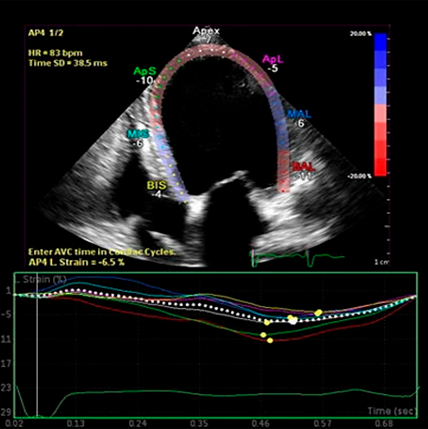

Como ingeniero especializado en el mantenimiento, instalación y reparación de equipos médicos, he tenido la oportunidad de trabajar con una amplia variedad de ecógrafos en centros médicos y clínicas a lo largo de todo Chile. Esta experiencia en terreno me ha permitido identificar los modelos que realmente se han ganado su lugar por su confiabilidad, calidad de imagen, disponibilidad de repuestos y facilidad de operación para los profesionales. Entre ellos destacan equipos como el Philips iU22, conocido por su excepcional resolución y su versatilidad clínica; el GE Vivid E9, altamente valorado en cardiología por su potencia en Doppler y capacidades 4D; y el Siemens X700, una opción sólida en clínicas de mediana y gran escala.

• IGE Vivid E9: Altamente valorado en cardiología y vascular por su excelente rendimiento en Doppler y su interfaz intuitiva.